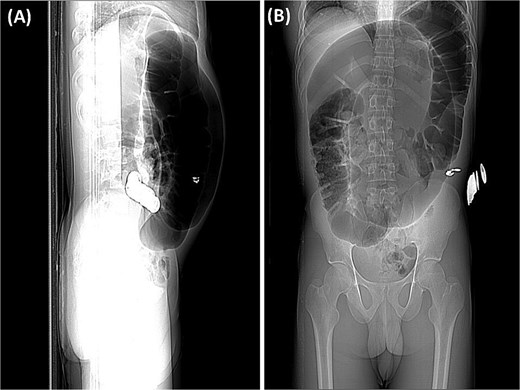

Abdominal radiography demonstrated classic features of sigmoid volvulus including dilated colonic loops, multiple air-fluid levels, and the characteristic coffee bean sign with absence of rectal gas. Computed tomography (CT) imaging (Figs 1 and 2) confirmed the diagnosis, revealing large gas-filled loops (maximum diameter 100 mm) without haustration and the typical mesenteric whirl sign, consistent with closed-loop obstruction. Initial management with colonoscopic decompression was attempted but proved unsuccessful, with persistent abdominal distension and tympani necessitating surgical intervention. Intraoperative findings confirmed a dolichosigmoid with mesenterico-axial volvulus, requiring sigmoid colon resection with creation of a double-barrel stoma using the Bouilly-Volkmann technique. Pathological examination of the resected specimen (30 cm in length, 491 g in weight) revealed flattened, hemorrhagic mucosa with vascular congestion and edema (Fig. 3). Microscopic analysis identified numerous Schistosoma eggs of varying morphology (Fig. 4A and B) within the submucosa and muscular layers, accompanied by granulomatous inflammation (Fig. 4C) and dense eosinophilic infiltrates. Chronic changes including eosinophilic microabscesses and calcified eggs were also noted (Fig. 5).

(A) The preliminary view on abdominal CT (scout view) revealed a distended sigmoid loop exhibiting an inverted U-shape, commonly recognized as the coffee bean sign. (B) The preliminary view on abdominal CT (scout view) showed dilated bowel loops.